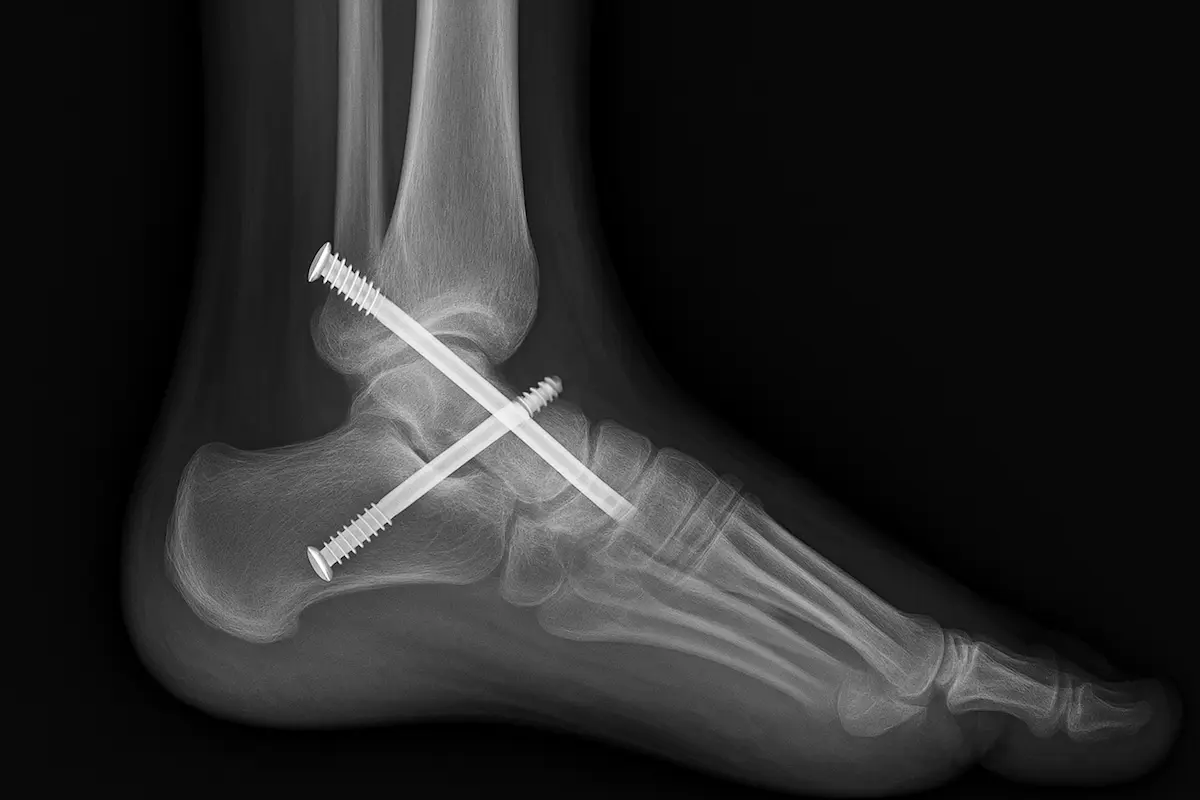

É um implante que substitui as superfícies desgastadas da tíbia e do tálus por componentes metálicos com um inserto de polietileno entre eles.

Como é feita a cirurgia

O procedimento é realizado em centro cirúrgico com anestesia regional ou geral. Veja as etapas:

- O cirurgião acessa a articulação por via anterior, faz cortes guiados na tíbia e no tálus e fixa os componentes metálicos.

- Um inserto de polietileno é colocado entre eles para permitir o deslizamento suave.

- Em casos selecionados, correções de eixo ou procedimentos nos ligamentos são feitos no mesmo ato para garantir alinhamento e estabilidade.